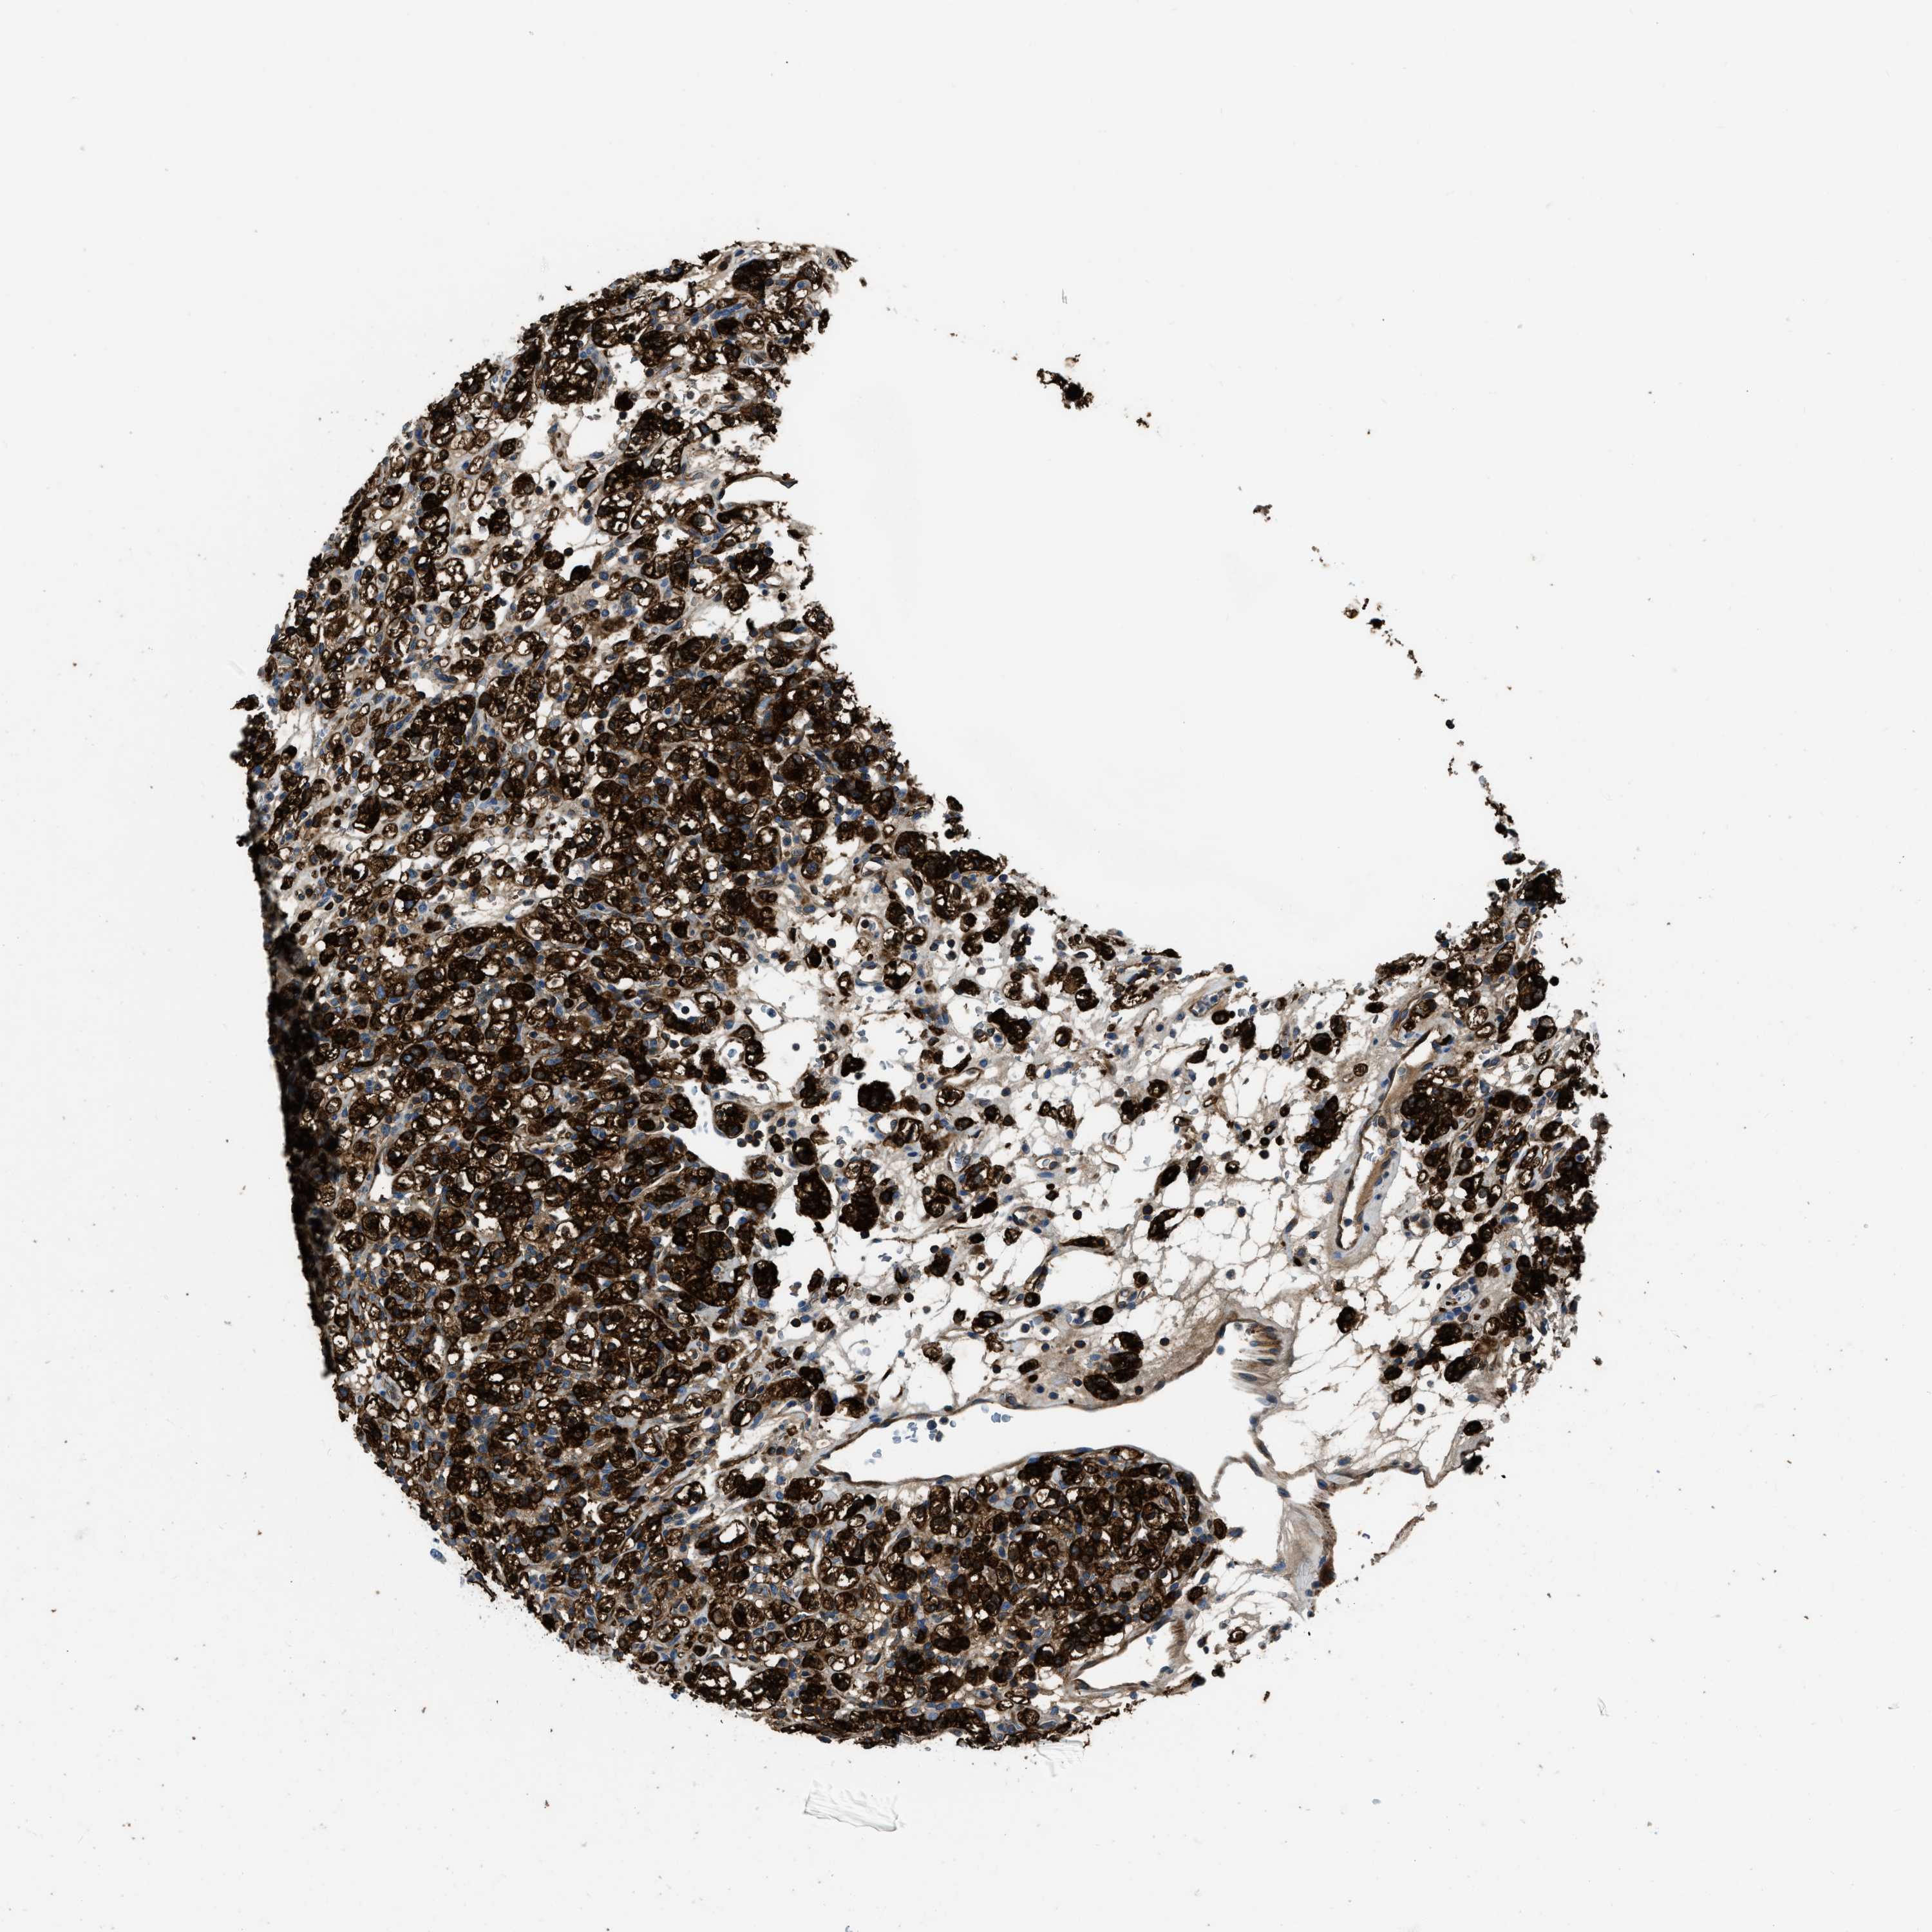

KIDNEY RENAL CLEAR CELL CARCINOMA (TCGA) - Interactive survival scatter ploti

The Survival Scatter plot shows the clinical status (i.e. dead or alive) for all individuals in the patient cohort, based on the same data that underlies the corresponding Kaplan-Meier plots. Patients that are alive at last time for follow-up are shown in blue and patients who have died during the study are shown in red.

The x-axis shows the expression levels (FPKM) of the investigated gene in the tumor tissue at the time of diagnosis. The y-axis shows the follow-up time after diagnosis (years). Both axes are complimented with kernel density curves demonstrating the data density over the axes. The top density plot shows the expression levels (FPKM) distribution among dead (red) and alive patients (blue). The right density plot shows the data density of the survived years of dead patients with high and low expression levels respectively, stratified using the cutoff indicated by the vertical dashed line through the Survival Scatter plot. This cutoff is automatically defined based on the FPKM cutoff that minimizes the p-score. The cutoff can be changed by dragging the vertical line or by entering a cutoff value in the square labeled "Current cut-off".

Under the Survival Scatter plot the p-score landscape (black curve; left axis) is shown together with dead median separation (red curve; right axis). Dead median separation is the difference in median mRNA expression between patients who have died with high and low expression, respectively. It is calculated as follows: median FPKM expression of dead patients with high expression - median FPKM expression of dead patients with low expression. This is intended to aid the user in visually exploring custom cutoffs and the associated p-scores and dead median separation.

Individual patient data is displayed and can be filtered by clicking on one or more of the category buttons on the top of the page. Categories describing expression level and patient information include: high, low, alive, dead, female, male and tumor stages. The scale of the x-axis can be toggled between linear and log-scale by clicking on the "x log" button. Mouse-over function shows TCGA ID, patient information and mRNA expression (FPKM) for each patient.

& Survival analysisi

Kaplan-Meier plots summarize results from analysis of correlation between mRNA expression level and patient survival. Patients were divided based on level of expression into one of the two groups "low" (under cut off) or "high" (over cut off). X-axis shows time for survival (years) and y-axis shows the probability of survival, where 1.0 corresponds to 100 percent.

PFKP is potential prognostic, high expression is favorable in Kidney Renal Clear Cell Carcinoma (TCGA)

Best expression cut offi

Based on the FPKM value of each gene, patients were classified into two groups and association between prognosis (survival) and gene expression (FPKM) was examined. The best expression cut-off refers the FPKM value that yields maximal difference with regard to survival between the two groups at the lowest log-rank P-value. Best expression cut-off was selected based on survival analysis .

When clicking on this number, the vertical dashed line indicating cut-off, the interactive survival plot, and the Kaplan-Meier curve will be adjusted to show results based on the best expression cut-off.

: 300.19

Average pTPM 309.2

Number of samples 521